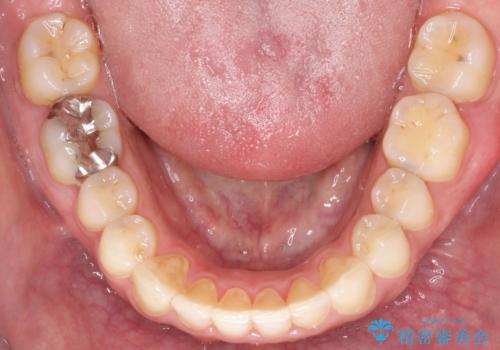

【インビザライン】前歯の隙間を閉じたい

- 前歯の隙間を主訴に来院されました。

マウスピース矯正にて、隙間を綺麗に閉じることができ満足していただきました。

前歯の隙間を閉じる際は、前歯部の突き上げが懸念されるため、適切な治療計画が必要となります。